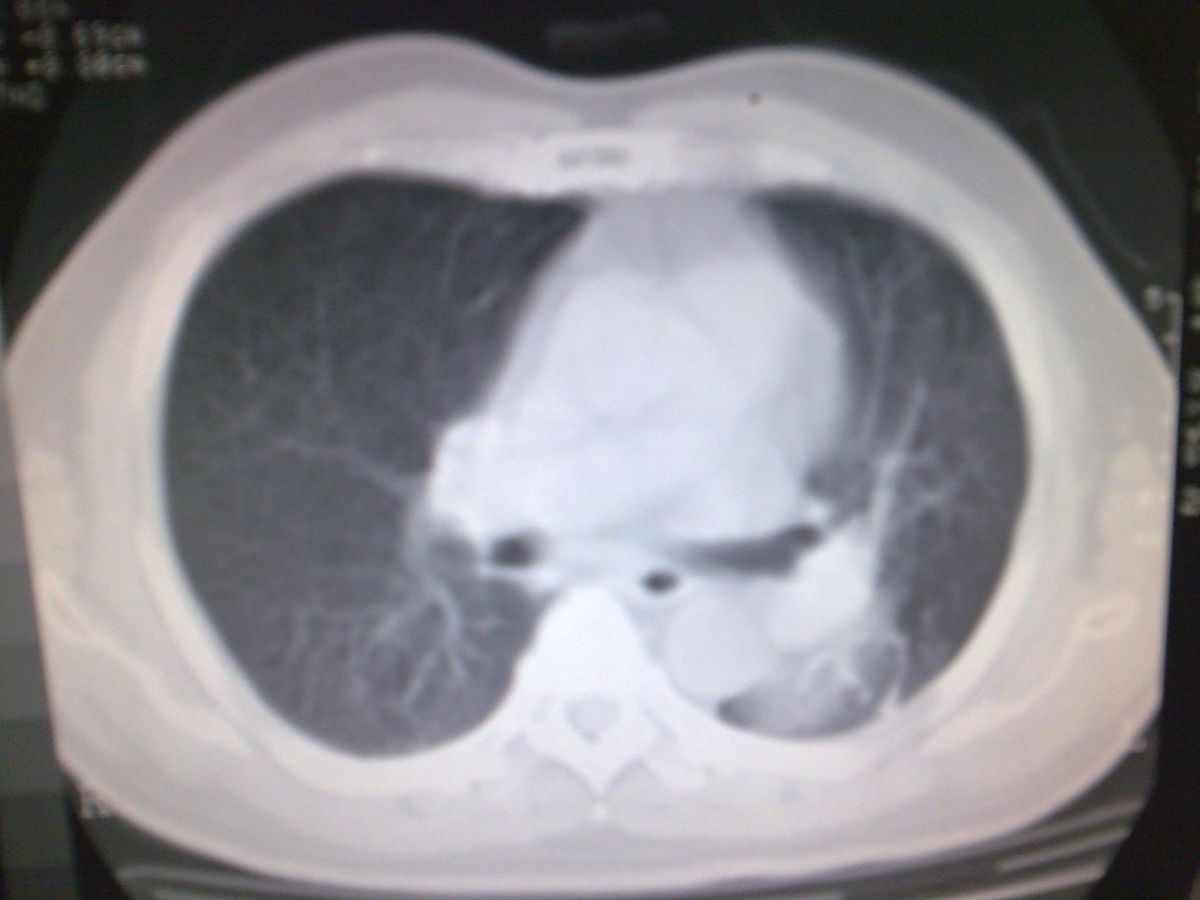

标题: CT19282:男性,70岁,咳血, [打印本页]

标题: CT19282:男性,70岁,咳血,

图片少了些,考虑周围性肺癌

考虑周围性肺癌

周围型肺癌。

考虑左下肺周围性肺癌。

考虑左下周围型肺癌可能性大。

考虑左肺下叶周围型肺癌可能。